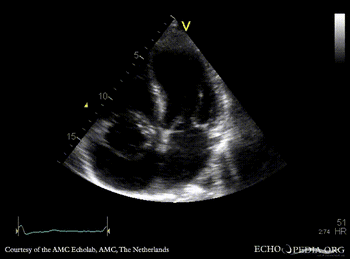

Case 37

Abscess of aortic root

Courtesy of: AMC Echolab, AMC, The Netherlands

E00270.jpg

PLAX: dilated aortic root, abscess of aortic root PLAX: dimensions of the abscess